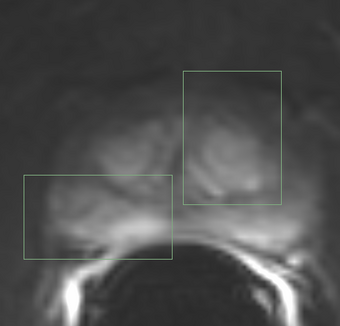

- ROI Mask Image (ROIMaskFileName): (Optional) Mask designating the voxels (non-zero) where the model should be fit. If not specified, the model will be fit to all voxels in the image.

- AIF Mask Image (AIFMaskFileName): Mask designating the location of the arterial input function (AIF). AIF can be calculated from a generic population AIF, the input using the aifMask or can be prescribed directly in concentration units using the prescribedAIF option.